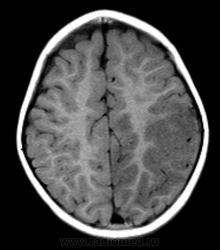

Ребенок 1 год 8 месяцев. В анамнезе с 06.12  многократные рвоты, повышение Т, слабость, сонливость, беспокойство, потиливость. БЫл поставлен диагноз ПТИ, после инфузионнйо терапии, дезинтоксикации в удовлетворительном состоянии выписана. Черезе месяц  гнойные высыпания на конечностях, диагноз пиодермия и дисфункция биллиарного тракта.  Полечили. Дальше в тчеении двух месяцев  однократные-многократные  рвоты, нарушение сна. Невропатолог поставил гидроцефальный синдрмо с тадии субкомпенсации. Ангиоретинопатия. На левой щеке на спине и на коже бедра гематомы в стадии отцветания. Сейчас состояние прогрессивно ухудшается.

Входящий диганоз пишут вирусный менингоэнцефалит. Рекомендуют диффреенцировать со свежими ишемическими изменениями и неопластическим процессом.

А что еще нужно? Диффузия есть, какой-то не очень понятный flair, зона изменений на них идентична Т2ВИ. По РКТ перед этим заподозрили арахноидальную кисту, диф с менингиомой задней трети серпа.

Артериальный инфаркт в бассейн не умещается, тут и сма и пма. Синусы на взгляд проходимы. Так что мне кажется больше за энцефалит. Оболочки правда не утолщены (если менингоэнцефалит).

Анамнез не дочитал сначала. За опухоль на мой взгляд данных нет вообще. Изменения идут по коре на большом протяжении с небольшой относительно зоной отёка белого вещества. Так что менингоэнцефалит наиболее вероятен. Анамнез ликвора на мой взгляд обязателен, хотя я и не невролог.

Я бы в дифряд еще гипоперфузию добавил (визуально похоже на PRES, но локализация иная)... Что там с магистральными сосудами? Ангио делали?

MELAS?

Масс-эффект есть - присмотритесь к бороздам на Т1. Есть поражение и коры, и белого вещества - такое бывает при нарушении кровотока по мелким сосудам. Снижение диффузии (я так понимаю, ADC снижен?) как раз говорит о цитотоксическом отеке и характерно для инфаркта. Единственное, что смущает - это вовлечение бассейна ПМА. Но, во первых, эти бассейны у людей вариабельны, и вполне может оказаться, что медиальные отделы полушария кровоснабжаются у этого пациента из СМА. А во-вторых, если есть патология сосудов, то почему бы и не поражение 2 бассейнов сразу? Так что, я не вижу тут ничего, что бы не укладывалось в инсульт. А посему пользуемся бритвой Оккама.

Энцефалит как правило двусторонний. Все эти болезни обмена - тоже множественные участки.